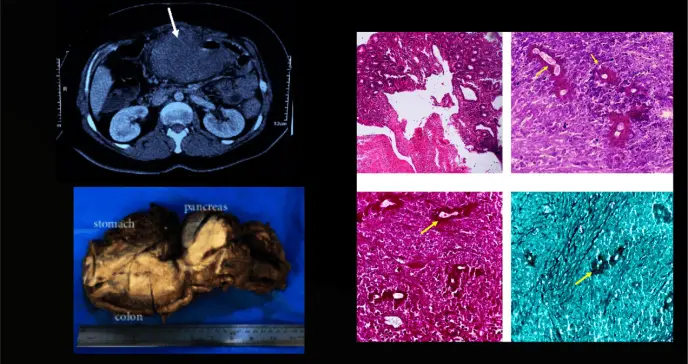

Por el contrario, los síntomas empeoraron, lo que motivó la realización de nuevos estudios mediante tomografía computarizada (TC). Estas imágenes mostraron una masa abdominal de apariencia maligna que envolvía el colon transverso, el estómago, la cola del páncreas y el riñón izquierdo.

Otras pruebas, como urea, creatinina, glucosa y funciones hepáticas, estaban dentro de rangos normales. Dada la sospecha de malignidad avanzada de colon basada en los hallazgos clínicos, radiológicos e histológicos previos, se decidió realizar una laparotomía exploratoria. Durante la intervención, se observó una afectación extensa de órganos viscerales, lo que requeriría una resección quirúrgica amplia.

La evaluación macroscópica reveló dos masas bien delimitadas, de consistencia gomosa y aspecto cremoso. La masa más grande, de 17 × 15 × 10 cm, se localizaba en la submucosa del colon y el páncreas, con extensión al estómago. El estudio histológico mostró cambios inflamatorios agudos y crónicos con una reacción predominantemente granulomatosa y un marcado aumento de eosinófilos.